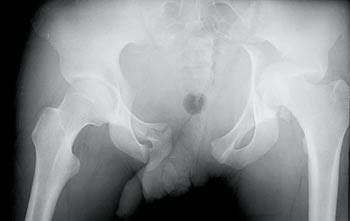

Pasient 2. En 29 år gammel motorsyklist kolliderte med møtende bil i høy hastighet. Luftambulanselege kom frem kort tid etter ulykken. Pasienten var da våken og hadde ubesværet respirasjon. Han angav smerter i ryggen og i underekstremitetene. Bekkenet ble vurdert som stabilt. Under transport ble pasienten klam og kaldsvett.

Ved innkomst i sykehus var pulsen 83 per minutt, systolisk blodtrykk 149 mm Hg og Glasgow Coma Scale var 15. Etter ca. 15 minutter var systolisk blodtrykk falt til 100 mm Hg. Rutinemessig røntgen av bekkenet viste ustabil bekkenfraktur (fig 2), og videre CT-utredning viste en dislokasjonsfraktur i os ileum på den ene siden og dislokasjon i iliosakralledd på den andre. I tillegg hadde han femurfraktur, lungekontusjon og nyrekontusjon. Man startet med operasjon av femurfrakturen og pasienten ble sirkulatorisk ustabil peroperativt. Laparotomi viste en liten venøs blødning. Etter hvert ble det anlagt en ekstern fiksasjon av bekkenet, og den kliniske situasjonen bedret seg. Definitiv kirurgi ble gjort ved en senere anledning. Pasienten har noe smerter, men er i arbeid.